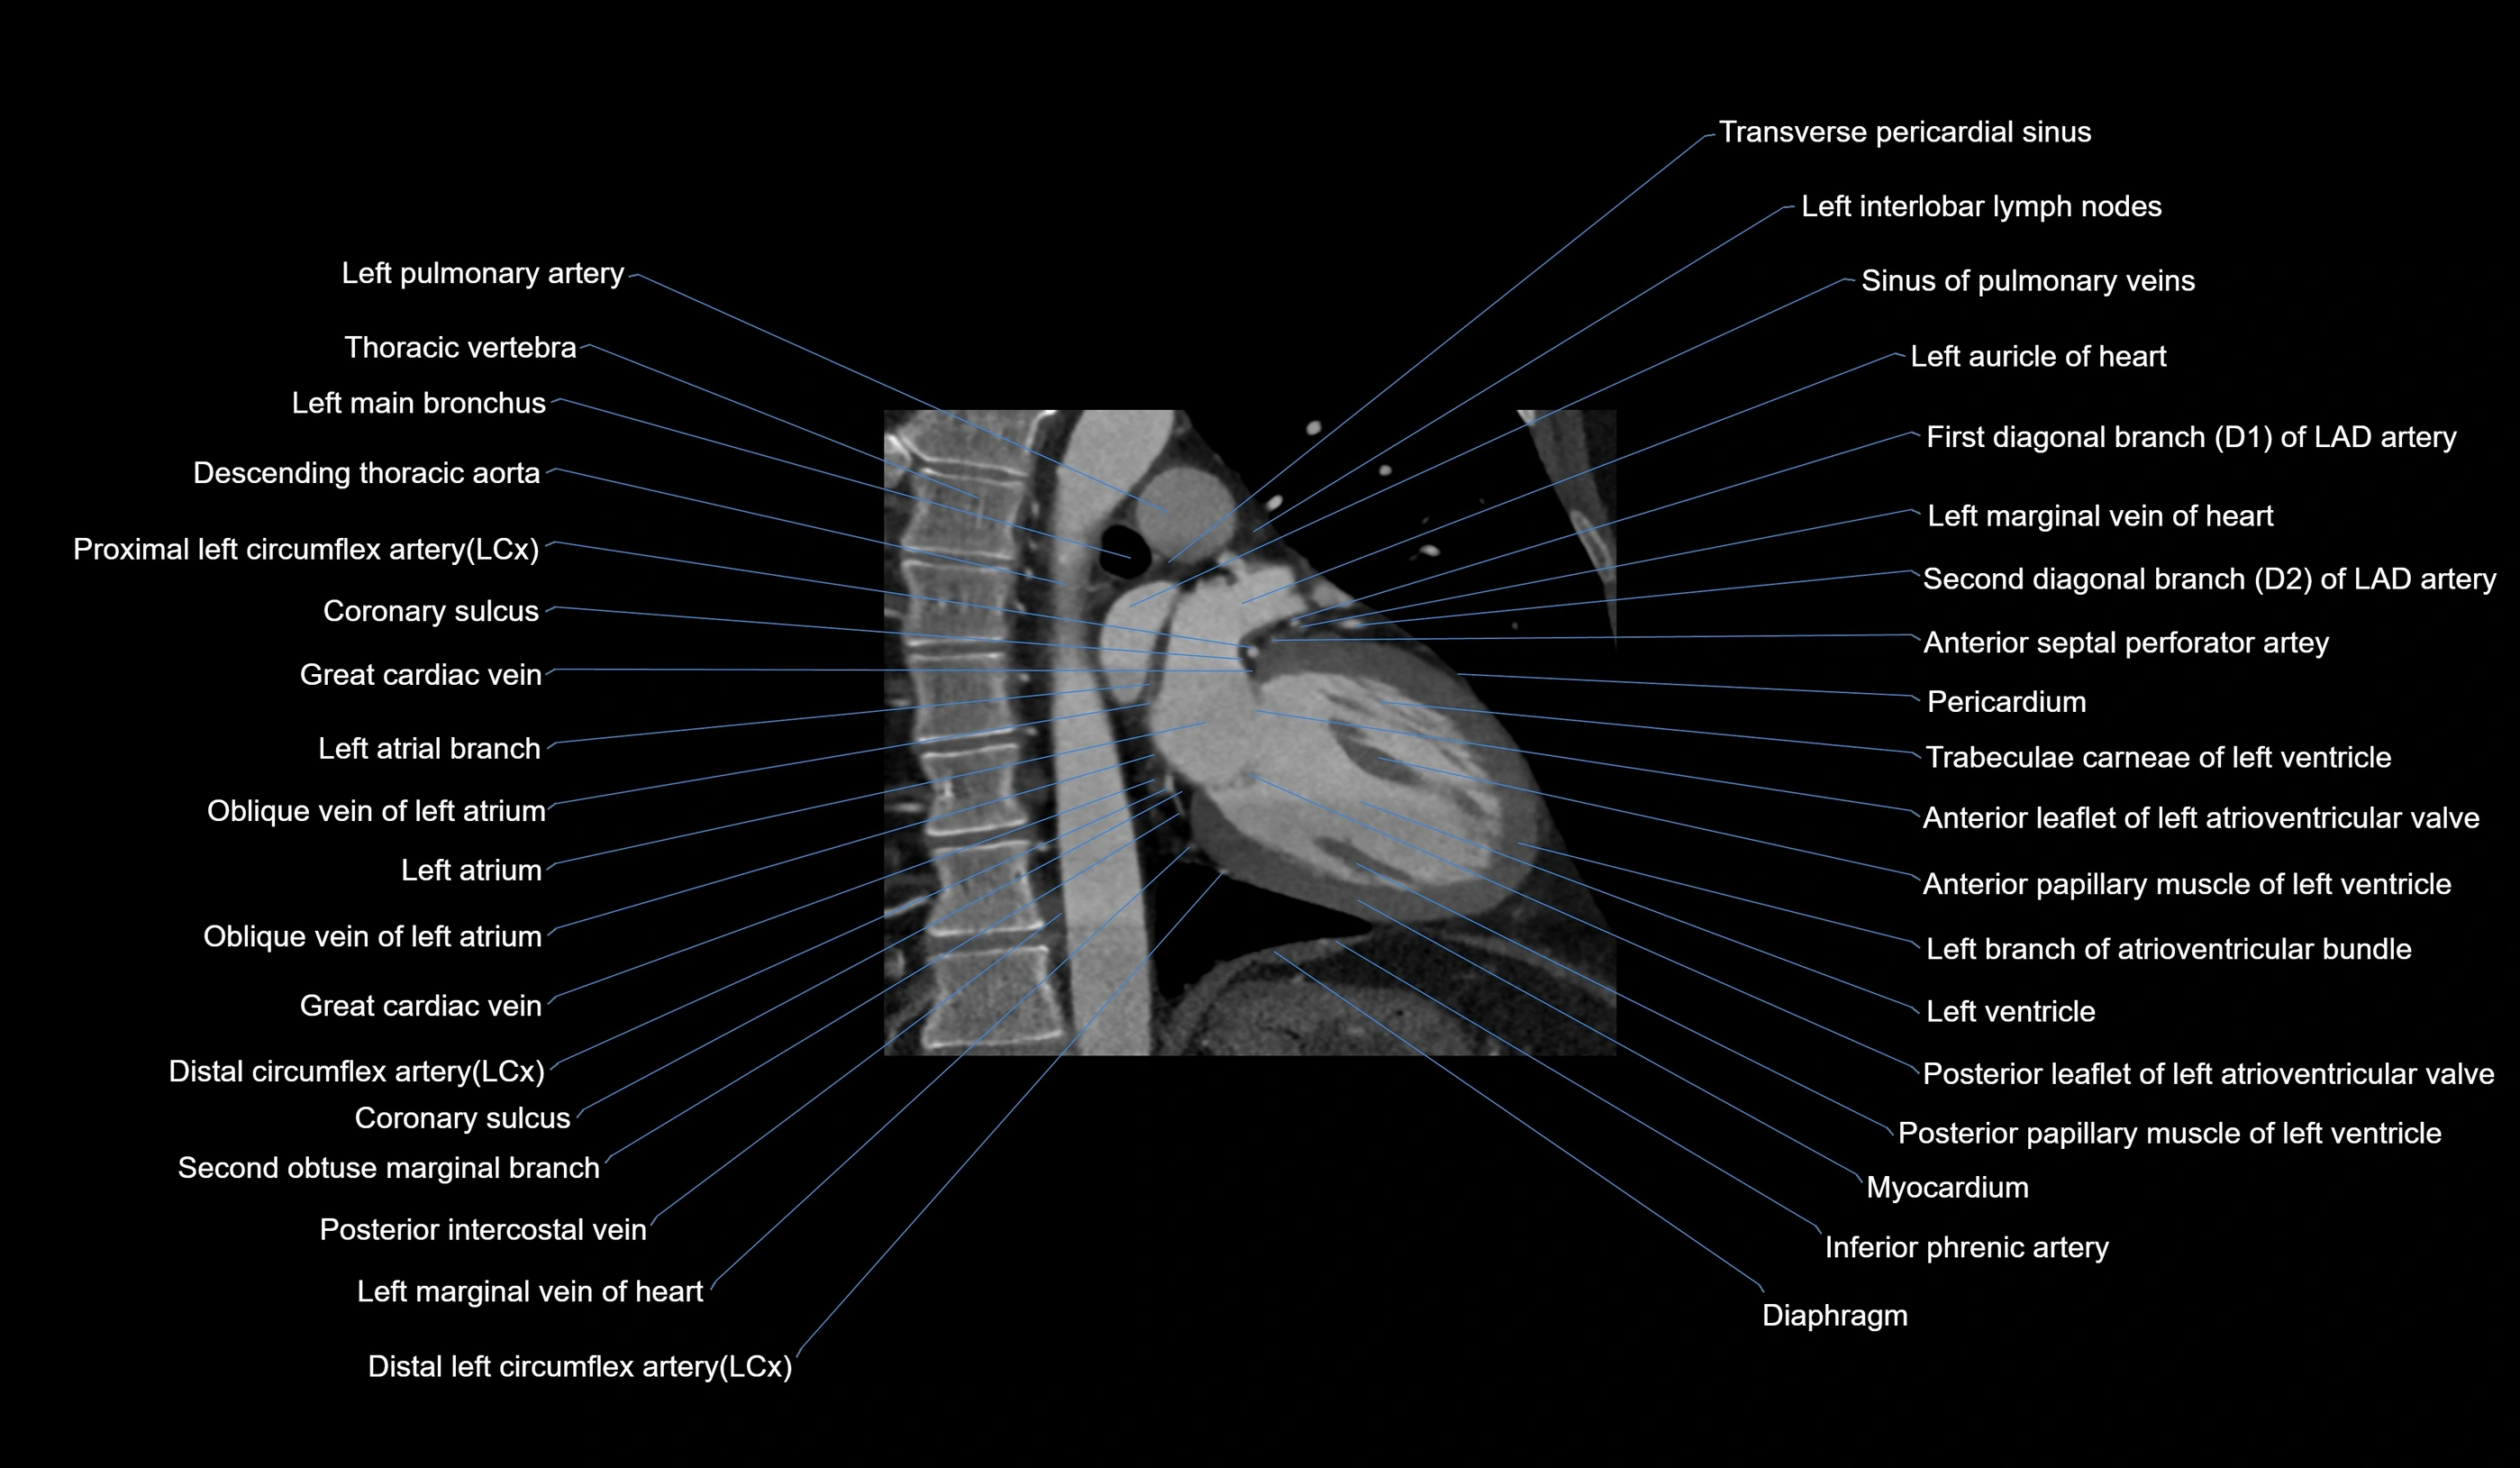

CT images